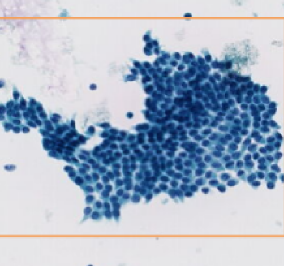

Block interception and precise amplification of gastric biopsy digital images; Tumor segmentation model

and heat map analysis; Feature extraction, negative and positive classification to predict tumor probability with high sensitivity.

1. Identification image: high-quality, direct, accurate, intelligent.

Identification Pattern

1. Normal tissue

2. Low & High grade

intraepithelial neoplasia

3. Adenocarcinoma

4. Signet ring cell carcinoma